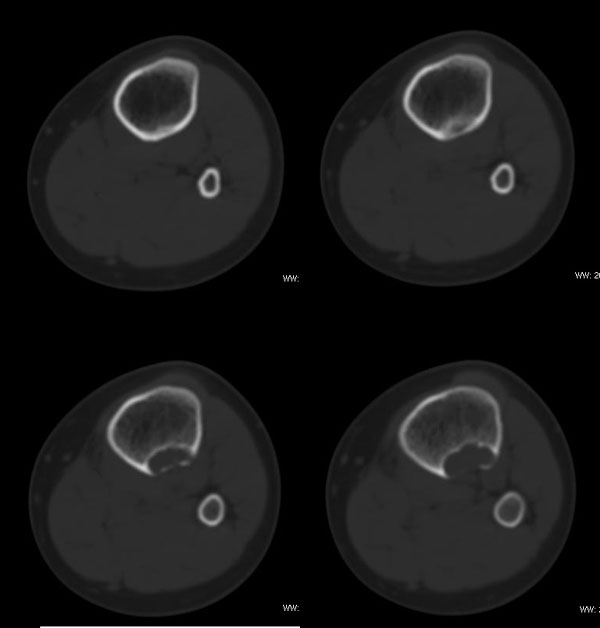

以下是引用37度在2010-1-7 12:22:00的发言:[br]左胫骨上段纤维性骨皮质缺损(非骨化性纤维瘤).

以下是引用dyqct在2010-1-7 14:54:00的发言:[br]考虑为左胫骨上段纤维性骨皮质缺损 ,可自愈.

以下是引用xkncyyhyq在2010-1-7 9:54:00的发言:[br]考虑为纤维性骨皮质缺损